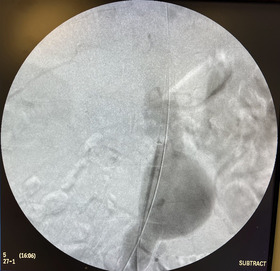

Ανεύρυσμα κοιλιακής αορτής

ενδαγγειακή αποκατάσταση

ελάχιστα παρεμβατική μέθοδος!!

24 Ώρες παραμονή στην κλινική!!